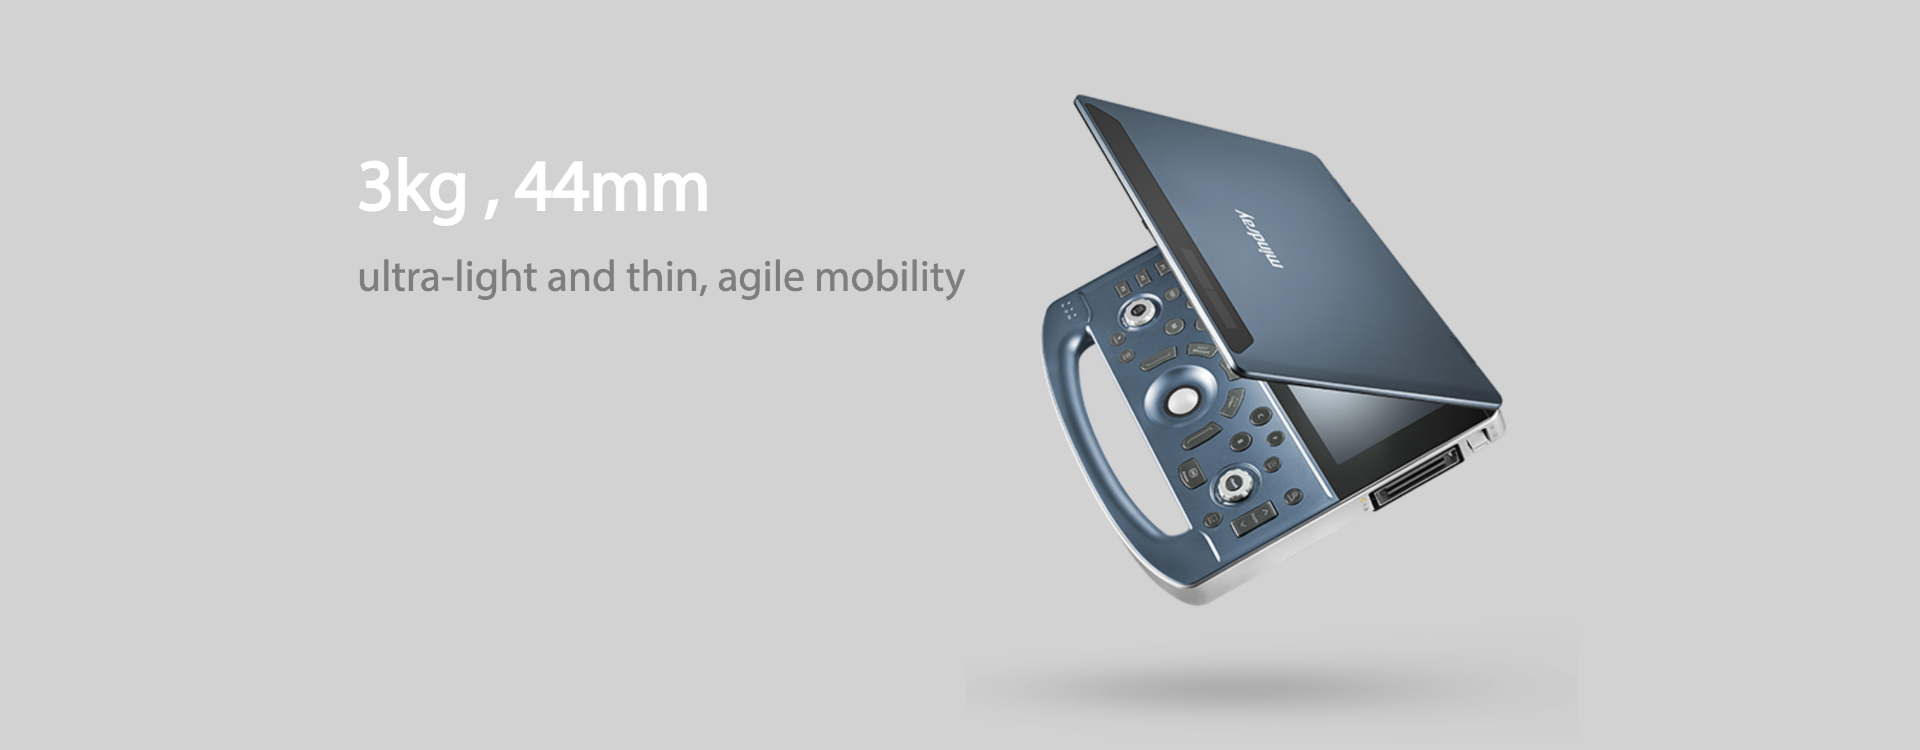

Light and Mighty

The MX7 from Mindray is an outstanding point of care ultrasound system. Designed with direct input from customers it offers the perfect combination of ground-breaking imaging technologies, a host of ergonomic features, and one of the lightest, thinnest, laptop design on the market.

Light AND mighty, the MX7 is a compact and ergonomic device with all the functionality you could need.